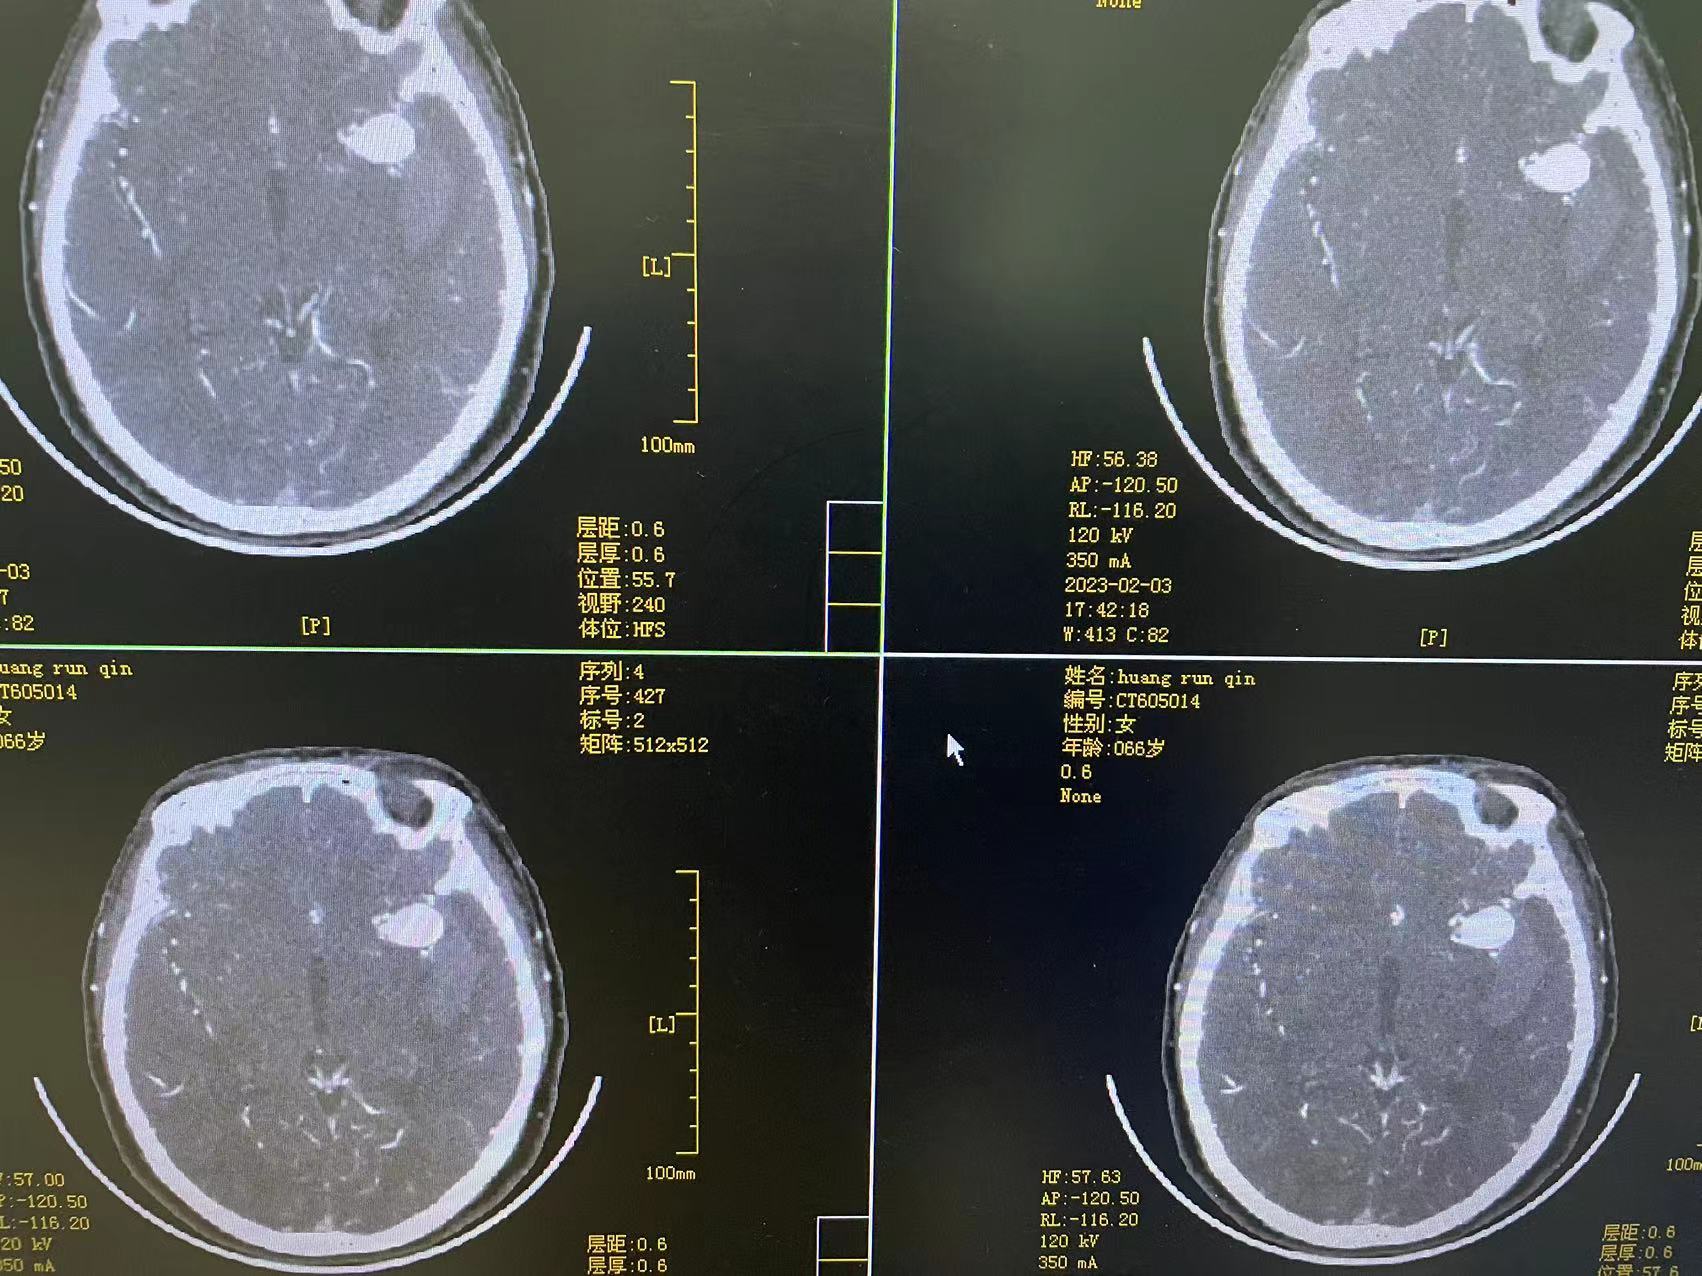

HRQ、女,66岁,463177,因头昏头疼2天,吐词不清1天于20230203日16时24分入院。右侧肢体肌力四级。

术后第一天